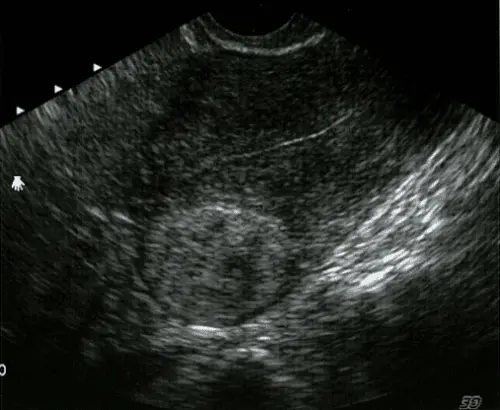

Mặc dù lành tính nhưng u xơ tử cung có thể gây ra nhiều phiền toái như đau bụng dưới, rối loạn kinh nguyệt, khí hư ra nhiều, đi tiểu liên tục hoặc táo bón. Nếu không được phát hiện và xử lý kịp thời, u xơ còn có thể ảnh hưởng nghiêm trọng đến khả năng mang thai và sinh sản, thậm chí gây thiếu máu do mất máu kinh nguyệt kéo dài. Do diễn tiến âm thầm và dễ bị nhầm lẫn với những triệu chứng khác, u xơ tử cung thường chỉ được phát hiện qua khám phụ khoa định kỳ hoặc siêu âm.

Bên cạnh u xơ tử cung, u quái buồng trứng cũng là loại khối u thường gặp ở phụ nữ trẻ từ 10-30 tuổi. Đặc điểm đặc biệt của khối u này là chứa các mô đặc trưng như tóc, răng, xương… dù đa phần lành tính nhưng cũng có nguy cơ biến chứng hoặc tiến triển thành ung thư trong một số trường hợp hiếm. Vì vậy, phụ nữ cần chú ý kiểm tra sức khỏe định kỳ, nhất là khi có các biểu hiện bất thường như đau bụng, chảy máu hoặc rối loạn kinh nguyệt.